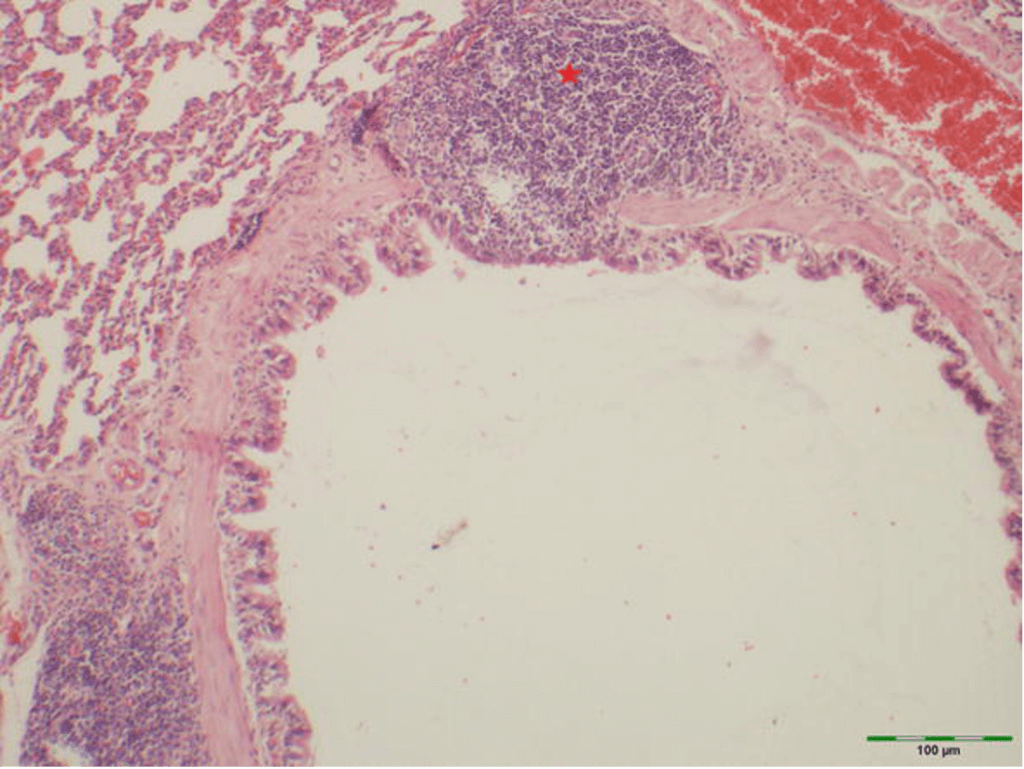

Mikroskopický rez malou prieduškou v pľúcach. Hviezda ukazuje na MALT zhluk, ktorý je plný imunitných lymfocytov